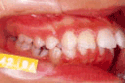

治療前後の比較

受け口

出っ歯

乱抗歯

開咬